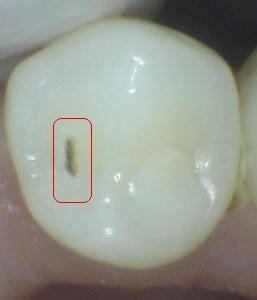

Sistema Internacional para la Detección y Evaluación de Caries (ICDAS)

¿Determine los códigos pertinentes a cada imagen?

Click en el hipervínculo: Para comparar el resultado de su diagnóstico